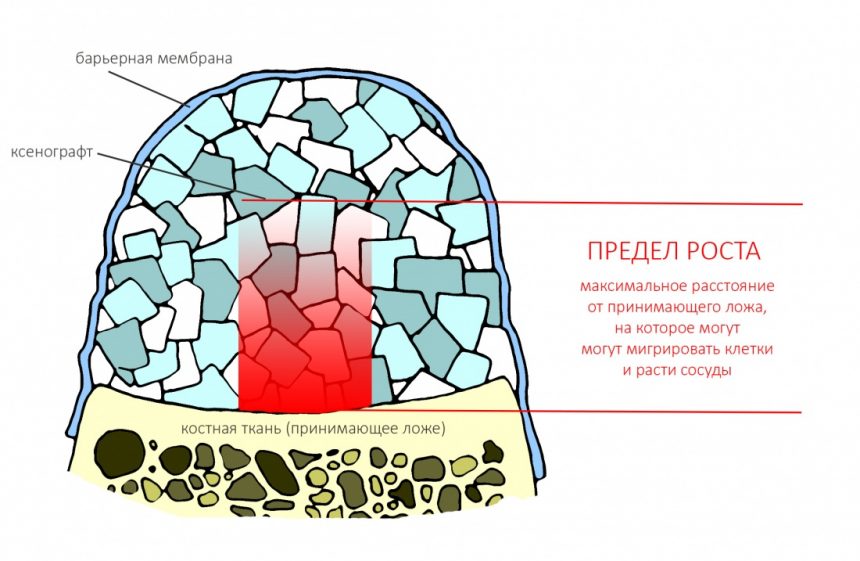

Вывод #1. У остеопластической операции с использованием чистых биоматериалов есть предел. Я называю его пределом роста. Он определяется скоростью и расстоянием миграции остеобластов и других клеток, участвующих в остеогенезе, ростом микрососудистого русла и т. д.: